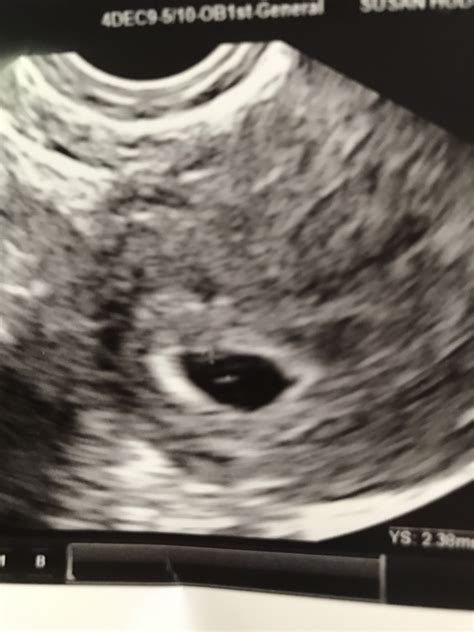

At five weeks, the embryo is still very small, measuring about 2 millimeters in length. The ultrasound will focus on detecting the gestational sac, which is a fluid-filled structure that houses the embryo. The presence of the gestational sac is a positive sign of pregnancy. Additionally, the ultrasound may reveal the yolk sac, which provides early nutrition to the embryo.

• Gestational Sac: This is the first structure that appears on the ultrasound. It looks like a small, dark circle within the uterus.

• Yolk Sac: This structure provides early nutrition to the embryo and is usually visible by the end of the fifth week.

• Embryo: At five weeks, the embryo is very small and may not be clearly visible. However, the presence of the gestational sac and yolk sac are positive indicators of a healthy pregnancy.